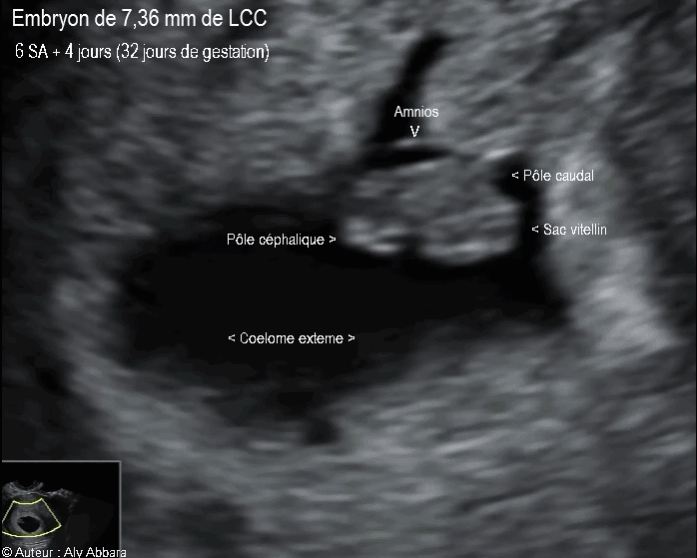

• Images échographiques montrant un embryon âgé de 32 jours de gestation (soit 6 semaines d'aménorrhée et 4 jours).

• La longueur crânio-caudale embryonnaire (LCC) = 7,36 mm

• La fréquence cardiaque calculée = 128 battements/minute.

• Ces images montrent un sac gestationnel composé essentiellement :

° d'une cavité cœlomique externe limité par le chorion qui s'insère sur l'endomètre ; cette cavité cœlomique externe contient :

* Un petit sac amniotique limitée par l'amnios et contenant

“ un embryon de 7,36 mm de longueur crânio-caudale avec deux pôles déjà différentiés : pôle céphalique et pôle caudal”

* Le sac amniotique juxtapose le sac vitellin qui se situe dans la cavité cœlomique externe.